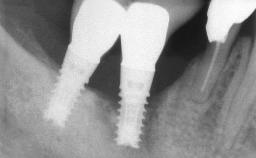

The fracture of an implant after it has been restored is one of the most severe complications. It most frequently occurs in partially edentulous jaws (1.5%). Most implant fractures involve implants with a diameter of 3.75 mm made of commercially pure titanium (Eckert 2010). Unfortunately, many cases are not reported or documented by the clinicians involved in resolving the problems created by the fracture. This case report describes the management of an implant fracture at site 36 in a middle-aged male patient. The implant had been restored with a screw-retained metal-ceramic crown.

Type of Implants Two-Piece

Bone Volume Horizontally and vertically sufficient